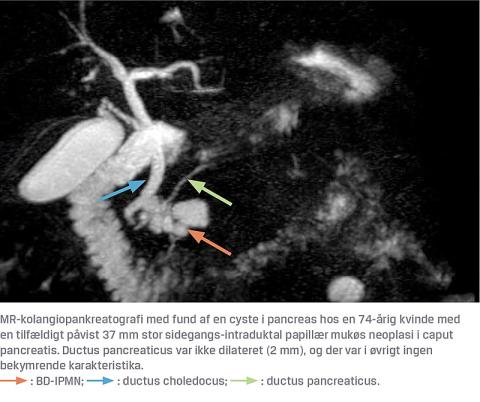

Der findes flere forskellige typer af cystiske læsioner i pancreas. I det følgende beskrives de tre hyppigste neoplastiske cyster og pseudocyster, som udgør langt hovedparten af alle cystetyper [9]. Det kliniske dilemma består grundlæggende i at skelne mukøse fra serøse cyster, idet sidstnævnte er benigne, mens de mukøse har et malignt udviklingspotentiale [6]. Intraduktale papillære mukøse neoplasier (IPMN) er epitelbeklædte [3] og typisk beliggende i caput eller corpus af pancreas. Patienterne er nogenlunde ligeligt fordelt mellem mænd og kvinder, og alderen er typisk 60-70 år på diagnosetidspunktet. Cysterne inddeles i hovedgangs-IPMN (MD-IPMN), hvis de opstår fra selve ductus pancreaticus, og sidegangs-IPMN (BD-IPMN). MD-IPMN har en betydelig højere risiko for malign transformation end BD-IPMN [10]. I flere studier af resecerede cyster har man fundet ca. 60% med high-grade-dysplasi (HGD) og invasivt karcinom ved MD-IPMN og ca. 30% ved BD-IPMN [3, 11] (Figur 1). En anden cystetype er de mukøse cystiske neoplasmer (MCN), som i modsætning til IPMN ikke har relation til udførselsgangene. MCN er epitelbeklædte, har et ovarielignede stroma og ses langt overvejende hos kvinder, typisk i 40-50-årsalderen. Læsionerne sidder hyppigst i corpus eller cauda af pancreas [9]. I et studie har man fundet en cancerprævalens på 17,5% efter resektion af MCN med øget risiko for invasiv vækst med stigende alder [12]. Serøse cystiske neoplasmer (SCN) hører til de nonmukøse neoplasmer og ses typisk hos kvinder (66%) i 60-70-årsalderen [9]. SCN er epitelbeklædte med forkalkninger og har oftest en bikagekonfiguration (mikrocystisk SCN) med en central ardannelse, men kan også forekomme oligocystiske og dermed billeddiagnostisk være vanskelige at adskille fra andre typer af cyster, især når de er små. De har ikke relation til udførselsgangen og findes overalt i pancreas [3]. SCN er typisk 6-10 cm i diameter, men kan variere fra 1 til 25 cm. SCN er benigne, men store cyster kan komprimere naboorganer og give tryksymptomer. Den rapporterede incidens varierer i forskellige opgørelser og ændres formentlig løbende i takt med forbedret billeddiagnostik og øget opmærksomhed. I et koreansk studie fra 2008 [13] angav man incidensen af IPMN, MCN og SCN ud af alle pancreascyster til hhv. 41%, 25% og 15%, mens man i et review fra 2015 påviste en incidens på hhv. 50%, 25% og 16% [14]. Pseudocyster er altid benigne og forekommer som sequelae efter både akut og kronisk pankreatitis. Cystevæsken er serøs og indeholder et højt niveau af amylase. Væggen består af fibrose- og granulationsvæv og er altså ikke epitelbeklædt (deraf betegnelsen pseudocyste). Patienterne er typisk mænd i 40-50-årsalderen [3, 9]. Selvom pseudocyster er benigne, kan de give smerter, trykgener, blive inficerede eller rumpere med læk af pancreassekret til abdominalhulen [9, 15].